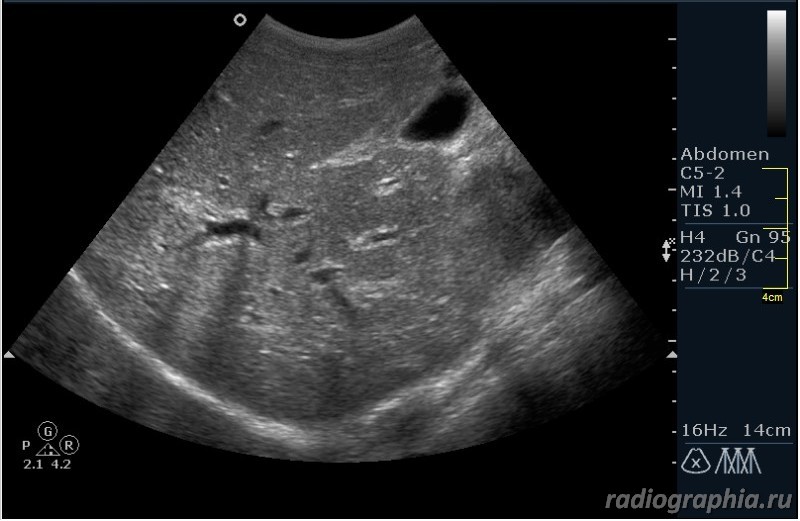

Как вы думаете, при какой патологии можно наблюдать такую сонографическую картину?

Похоже на расширенные внутрипеченочные протоки ,отек стенок ж.пузыря--может быть при остром гепатите

Гепатиты - такой ответ автор считает верным.